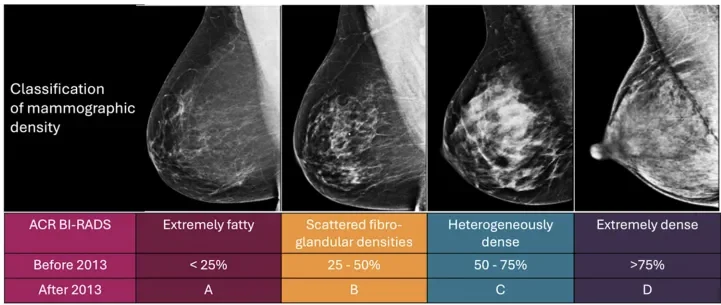

乳房由腺体组织(致密组织)和脂肪组织组成。致密乳腺意味着乳房中腺体组织所占的比例更高。这需要通过乳房X光摄影(钼靶) 来判断,通常报告会分为四个等级。

· 筛查难度更大:在传统乳腺X光检查下,致密的腺体组织在影像上是白色的,而早期的癌症病灶同样表现为白色,这就好比“雾里看花”或“雪地里找白熊”,极易造成漏诊。